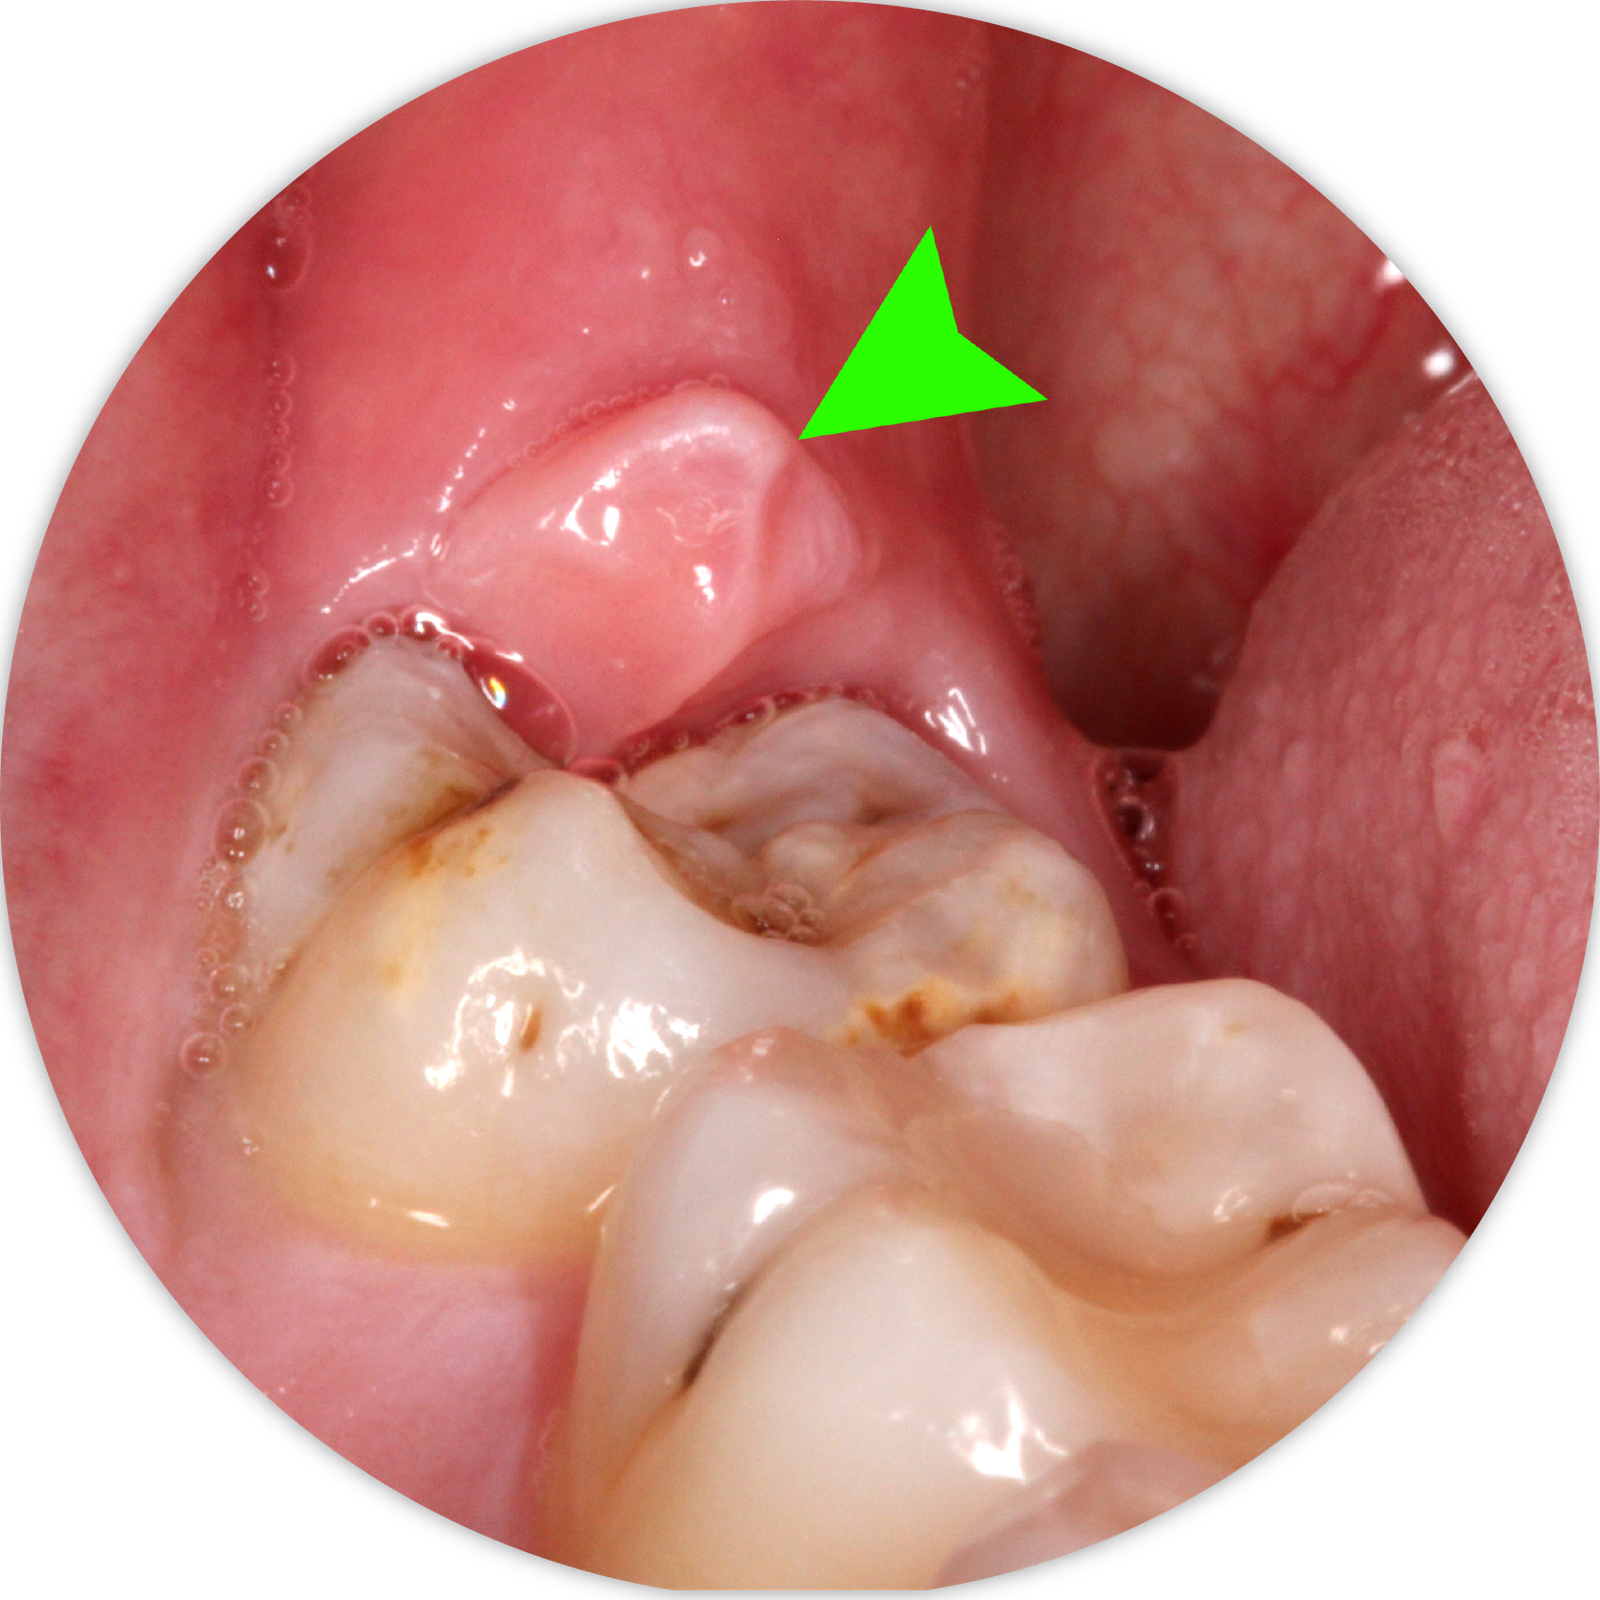

Răng khôn hay còn gọi là răng số 8, là những chiếc răng mọc ở phía trong cùng hai hàm răng ở những người trưởng thành trong độ tuổi trung bình từ 17- 25. Vì cấu trúc xương hàm người Việt chúng ta thường nhỏ, răng khôn không có đủ chỗ để mọc thẳng, dẫn đến tình trạng mọc lệch, mọc 1 phần, đâm xiên vào răng bên cạnh. Điều này dẫn đến nguy cơ kẹt thức ăn, viêm nướu, sâu răng, áp xe hoặc thậm chí là sưng viêm 1 bên mặt. Chúng tôi khuyến nghị khách hàng nên đi nhổ răng khôn từ giai đoạn răng mới mọc nhằm tránh các biến chứng và cơn đau.

Răng khôn có thể được nhổ trước hoặc sau khi thấy răng này mọc trên cung hàm. Trước khi mọc trên cung hàm, vị trí răng khôn được thể hiện trên phim X-quang toàn cảnh. Bác sĩ sẽ chỉ định nhổ răng khôn nếu tiên đoán răng sẽ mọc kẹt, mọc lệch, có nguy cơ gây biến chứng. Sau khi thấy răng khôn đã nhú hoặc mọc, khách hàng có thể đến thăm khám và nhổ răng khôn. Việc nhổ răng nên được tiến hành trước khi vùng răng này bị viêm sưng. Nếu có tình trạng đau, sưng và viêm, bác sĩ sẽ kê toa thuốc trước khi tiến hành nhổ răng.